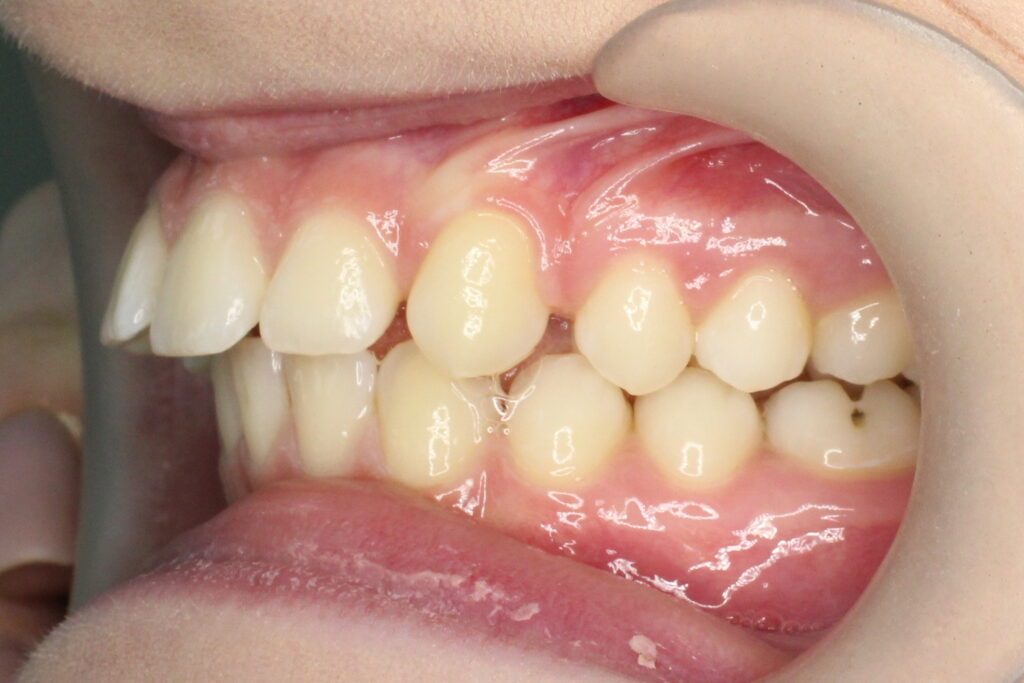

Ситуация до лечения

Диагноз: дистальный прикус, сужение, удлинение верхнего зубного ряда, скученность фронтальной группы зубов на нижней челюсти. Лечение проводилось самолигирующей брекет-системой Damon Q, срок лечения составил 2 года и 2 месяца.

Ситуация до лечения брекетами